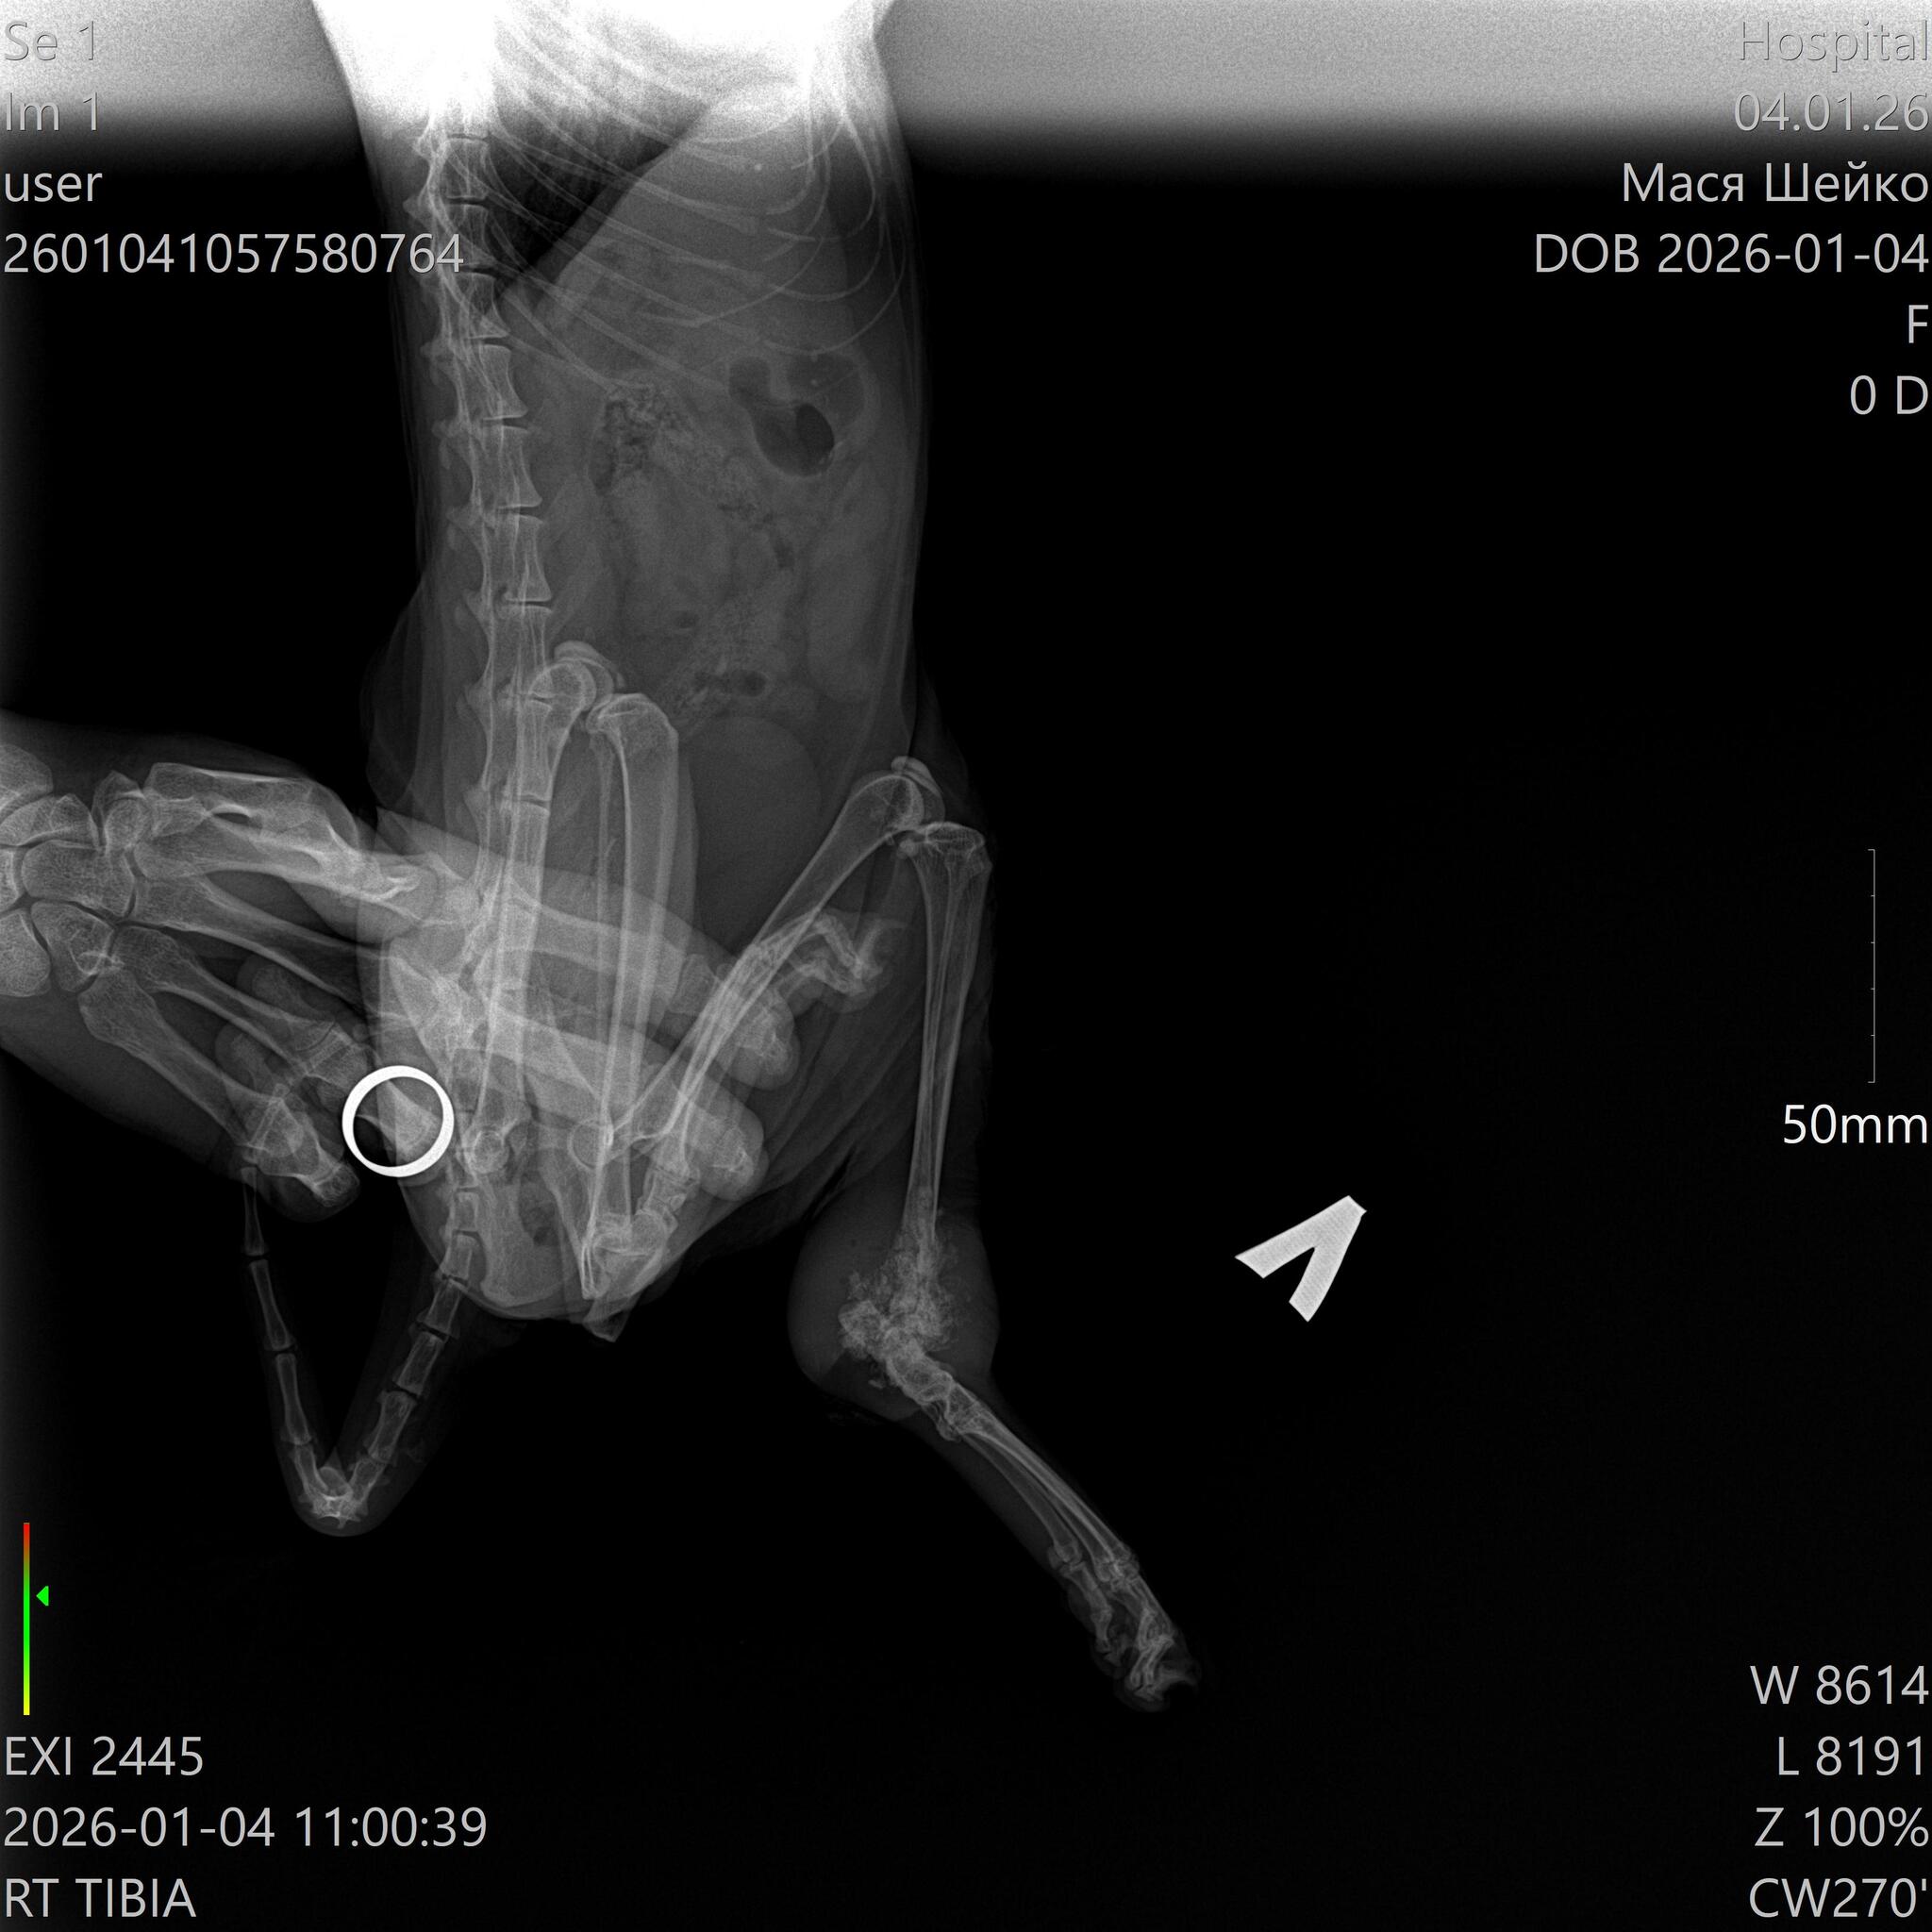

Короче, 2 января мы ее забрали из деревни, показали врачу. Вчера сделали рентген, сегодня показались онкологу. Остеосаркома. Скакательный сустав разрушен. Единственный выход - ампутация. Завтра операция.

Рентген